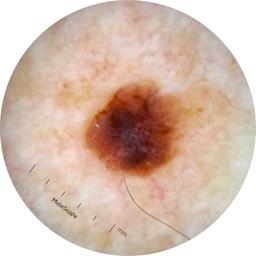

ISIC_6813604

MEL-SELF Trial, https://www.sydney.edu.au/medicine-health/our-research/research-centres/melself-project.html

acquisition_day 624

age_approx 75

anatom_site_1 Head and neck

anatom_site_general head/neck

diagnosis_1 Benign

diagnosis_confirm_type single image expert consensus

fitzpatrick_skin_type I

image_type dermoscopic

personal_hx_mm True

sex male